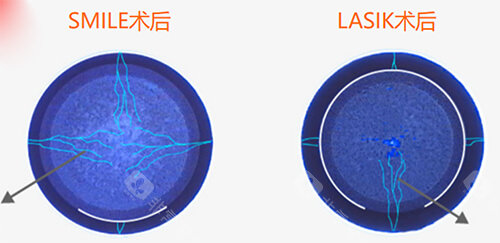

联合手术常态化

2025年临床数据显示,交联术联合屈光手术的患者占比高,术后角膜稳定性提升。